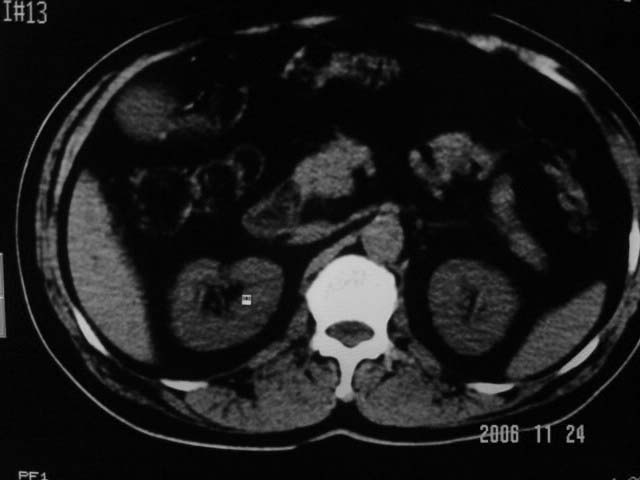

标题: CT5395:男、60岁,皮肤、巩膜黄染伴上腹部疼痛20天 [打印本页]

标题: CT5395:男、60岁,皮肤、巩膜黄染伴上腹部疼痛20天

劳烦各位老师看一下最后一幅箭头指的地方是不是胆总管结石.ct值约63hu.

感觉不是结石可能,与上一层面联系应该是门脉区影像,图像显示不佳,胆总管显示不清[特别是胰头以上段],目前影像只能说肝内外胆管扩张,胰管扩张,胆囊扩大。提示胆总管远端梗阻。可考虑肿瘤或结石所致

胆总管内结节状高密度灶,边缘隐约可见低密度环绕,首先考虑结石伴肝内胆管扩张; 2、胆囊增大,胆囊炎

肝内外胆管及胰管均示有扩张,胆囊增大.提示胆总管远端梗阻,可考虑肿瘤或结石或肿瘤伴结石,建议强化扫描